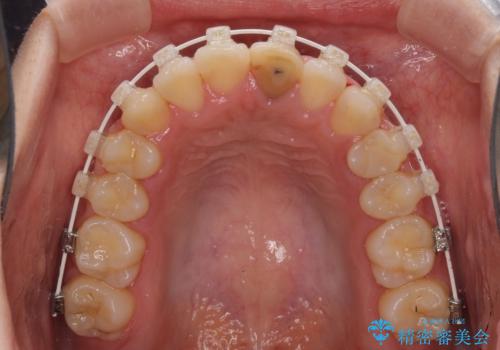

前歯のクロスバイトと変色した歯 ワイヤー矯正とセラミック治療

- 前歯のクロスバイトと神経を取り除いた後に変色してしまった前歯を気にして来院された患者様です。

ワイヤー矯正により矯正治療を行った後に、前歯の補綴治療を行うこととしました。

変色してしまった前歯は、反対側の歯と比べて歯肉が覆い被さっていたため、骨整形を含めた歯周外科処置を行い、歯肉ラインを整えることとしました。

インビザラインでの矯正治療も十分に対応可能でしたが、自己管理の煩わしさから、ワイヤー矯正を行うこととしました。

歯周外科処置を行うかどうかは非常に悩んでいらっしゃいましたが、範囲がそれほど広くないため術後の痛みも強くないだろうということで、処置を行うこととなりました。